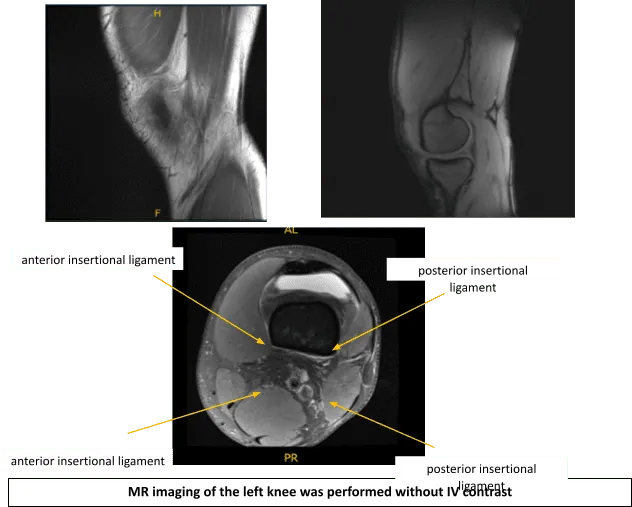

Se realizó una resonancia magnética. Existe una compleja ruptura del menisco lateral con desplazamiento de la mayor parte del cuerno posterior y la unión cuerpo-posterior desplazada anteromedialmente, inmediatamente posterior al cuerno anterior.

Se forma quiste intrameniscal tanto en el menisco desplazado como en el cuerno anterior nativo, con un grupo de quistes parameniscales que mide anteriormente hasta 1,2 x 1,4 x 1,5 cm (dimensión craneocaudal x anteroposterior x transversal). Existe una pérdida de cartílago de grosor total sobre el aspecto central de soporte del cóndilo femoral lateral, abarcando aproximadamente 1,4 x 0,5 cm con un colgajo de delaminación no desplazado medialmente.